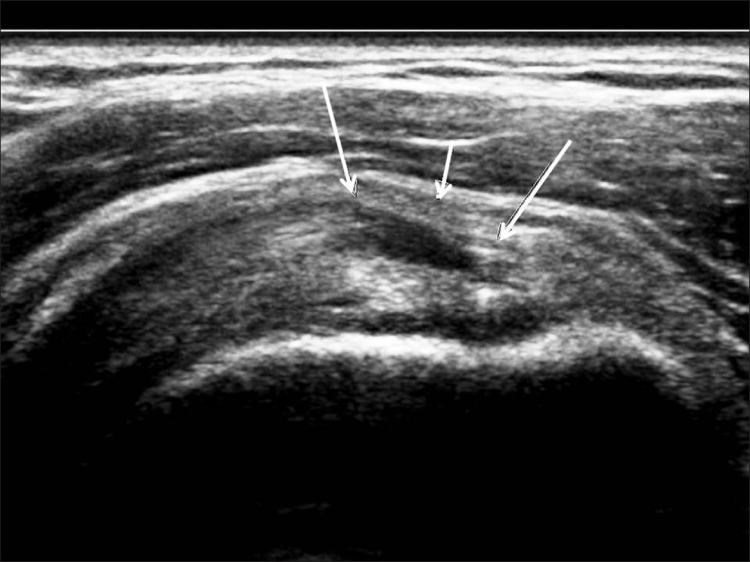

Los desgarros del manguito de los rotadores son la patología más común que se encuentra en los exámenes de ultrasonido del hombro.[7] La incidencia de lágrimas aumenta con la edad. Los desgarros de tendones se pueden clasificar de acuerdo con el grado de falla de la fibra, que van desde desgarros completos [Figura 7], desgarros de espesor total [Figuras 8, 9], desgarros de espesor parcial [Figuras 10-12] y desgarros intrasustancia [Figura 13 ]. Un desgarro agudo suele ir acompañado de derrame articular o bursal [Figura 12]. [7-9] La ausencia de derrame generalmente se relaciona con desgarros crónicos.[9] En un metanálisis sobre la precisión de la resonancia magnética, la artrografía por resonancia magnética y la ecografía en el diagnóstico de desgarros del manguito de los rotadores, la ecografía ofreció una alta sensibilidad y especificidad para la evaluación de los desgarros del manguito de los rotadores de espesor total (92,3 y 94,4 %, respectivamente) con 85,1 % y 92 %, respectivamente para todas las lágrimas.[7] El desgarro de espesor parcial aparece como un defecto o hendidura hipoecogénica en el tendón, afectando solo una parte de su espesor, mientras que un desgarro de espesor total se extiende desde la bolsa hasta la superficie articular del tendón. Un desgarro completo es un desgarro de espesor completo que afecta todo el ancho del tendón. El tendón se retrae medialmente, y la cantidad de retracción depende de la edad del desgarro. En las roturas crónicas, el tendón desaparece por debajo del arco coracoacromial, dejando la cabeza humeral descubierta por el supraespinoso, el denominado signo de la "cabeza desnuda". Los hallazgos de la ecografía incluyen la falta de visualización del tendón y la hernia del músculo deltoides. Los desgarros intrasustancia permanecen localizados en el tendón sin afectar sus márgenes. Los desgarros intrasustancia y de espesor parcial pueden ser difíciles de diferenciar de la tendinopatía focal.